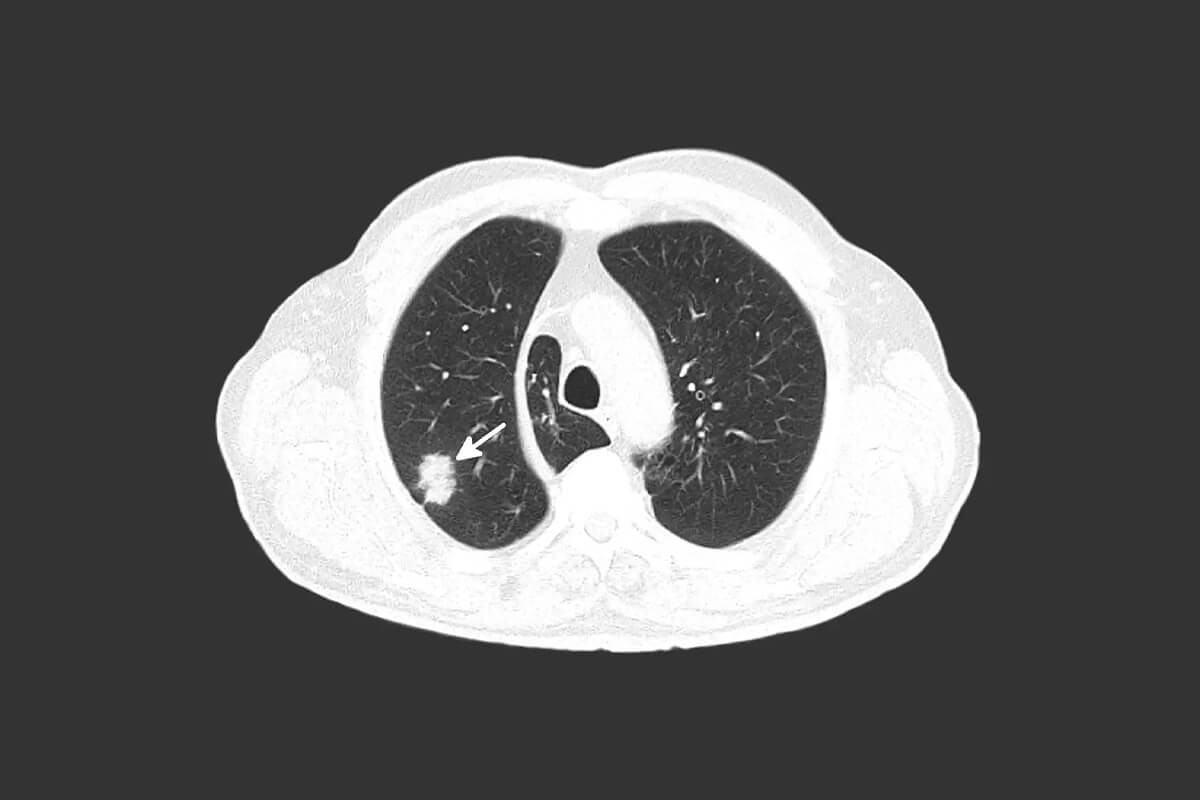

Advanced Lung Cancer Screening

You may qualify for low dose CT (LDCT) lung cancer screening if you’re 55 to 77 years old, have no symptoms of lung cancer, currently smoke (or quit within the past 15 years), and have a 30-year history of heavy smoking. If you think you qualify or have a prescription from your doctor for LDCT lung screening, please call to speak with a scheduler.

Technology Spotlight

Adventist Health Glendale has long been at the forefront of offering programs and cutting-edge technology for early detection of a wide range of conditions. The adoption of DynaLync and DynaCAD Lung provides critical tools to aid with the identification, tracking, and management of relevant information to help physicians reach a quick and definitive diagnosis. We utilize low dose CT (LDCT) lung screening, which is quick and easy and results in a minimal amount of radiation exposure. We are determined to raise awareness and improve access to this testing for all people at high risk. Therefore, we are currently offering LDCT lung screening to individuals who meet established high-risk criteria.